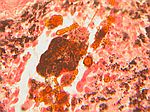

Asbestose, Ke.rot